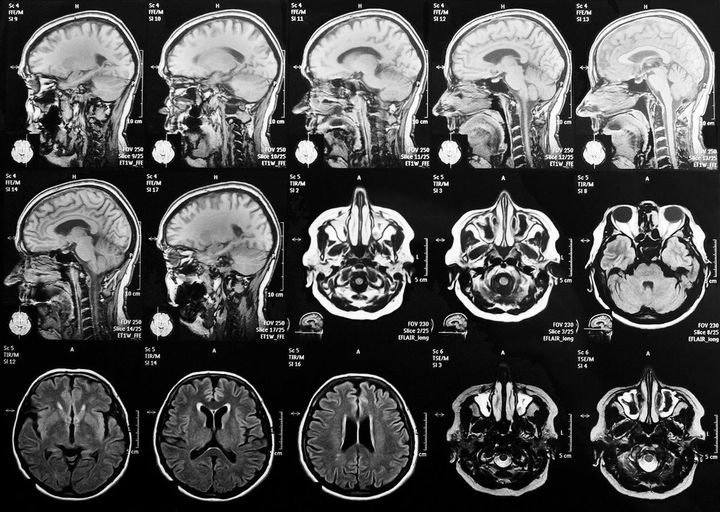

「7月頃母は、『頭がボーッとする。なんだか自分がおかしい』と訝しんでいて、『心配だから、一度病院で診てもらおう』と言ったらすんなり受診することになりました。本人も不安だったんだと思います。脳神経外科でMRIを撮ってもらった結果、脳の萎縮がみられることと、日常生活の状態を話したうえで、『アルツハイマー型認知症』の診断を受けました」

頭部のMRI画像

※写真はイメージです